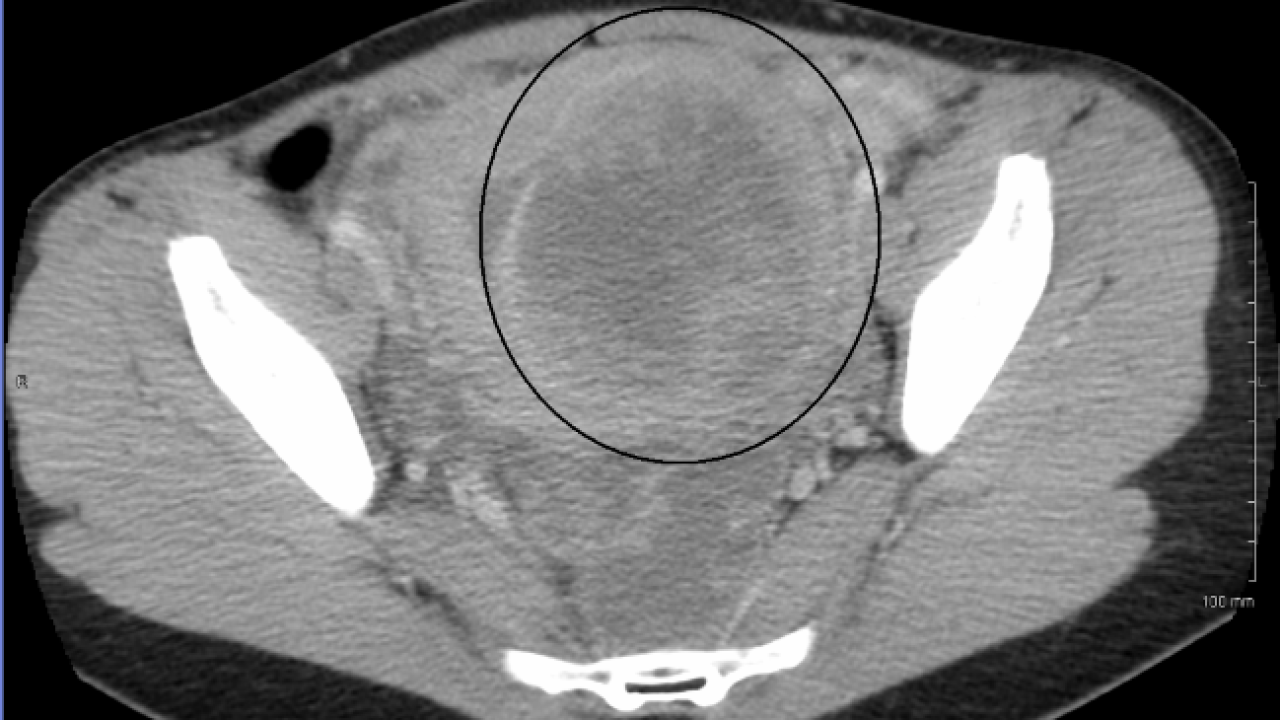

Tanıda venöz doppler ultrasonografi ve BT venografi gibi yöntemlerden yararlandıklarını aktaran Dr. Tümkaya, uygun hastalarda ise anjiyo yoluyla yapılan embolizasyon işlemi sayesinde sorunun cerrahiye gerek kalmadan çözülebildiğini ifade etti.